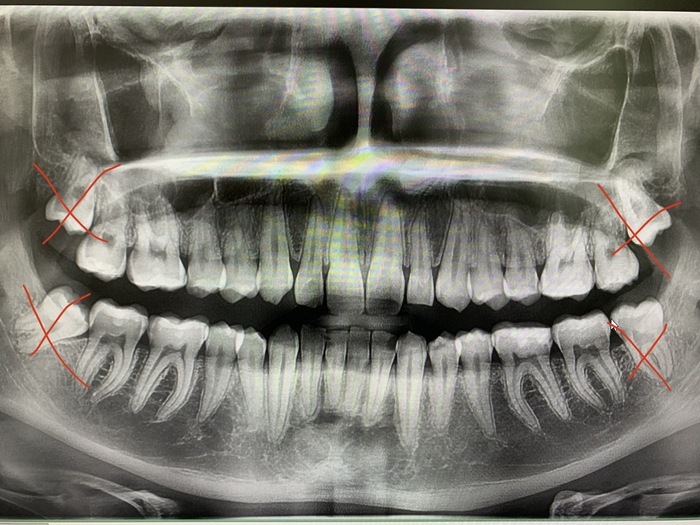

Сага о стоматологии. Глава 37. Можно ли удалить сразу все зубы мудрости за один раз?

Для ЛЛ: можно, но не всем и не всегда.

Ясное дело, что разом все восьмерки, которые полностью лежат в кости, я не взялся бы удалять в амбулаторных условиях сразу даже себе, так как риск осложнений крайне высок, а пациент потом на утро проклянет весь твой род до пятого колена, так как потом будет ПИСЕЦ КАК ПЛОХО. Как вот тут.

Теперь рассмотрим один из примеров. Вчера это был крепкий 18-летний парень, сын медсестры, он абсолютно здоров и готовится к службе в армии, куда уезжает через недели 3. Но вот беда, начали резаться зубы мудрости, а пользоваться потом услугами военной карательной стоматологией где-то у черта на рогах желания нет. Он стойко переносит все тяготы службы и лишения военной службы любого лечения, да и в случае чего мама ужалит дома необходимым препаратом.

Его восьмерки лежали под десной, но кость пилить не приходилось, поэтому удаление всех четырех зубов прошло за минут 30

Положили тромбоцитарную массу, ушили, дали рекомендации, отпустили.